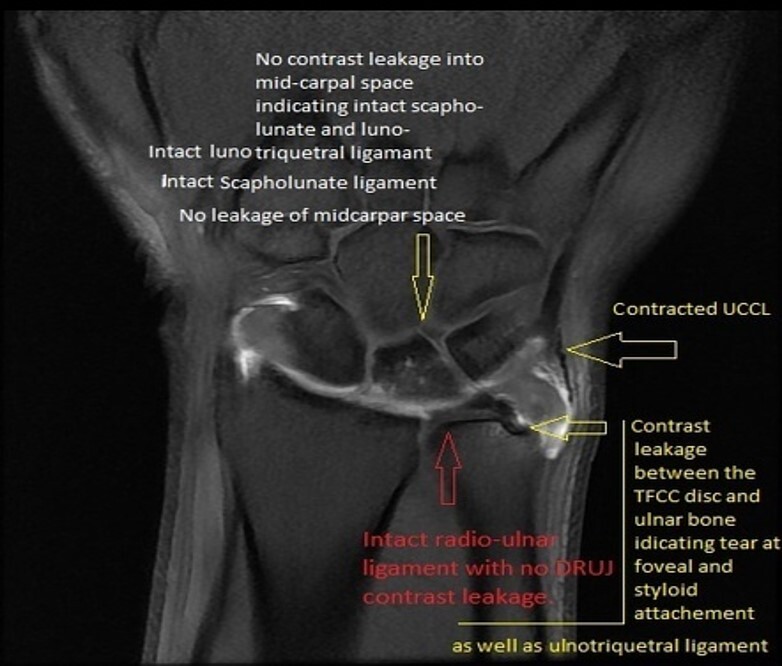

Wrist: TFCC Tear

What the TFCC is: Triangular fibrocartilage complex

Ulnocarpal ligaments

Subsheath of extensor carpi ulnaris tendon

Radioulnar ligaments

Central fibrocartilaginous disk

Pathophysiology: Tear from a fall onto an outstretched hand or other high-force wrist loading trauma. Can also be the result of degeneration.

MRI should confirm TFCC tear; might need arthrogram,

CT or MRI with contrast

Arthroscopy can also be performed

contrast should not be freely flowing, should be contained